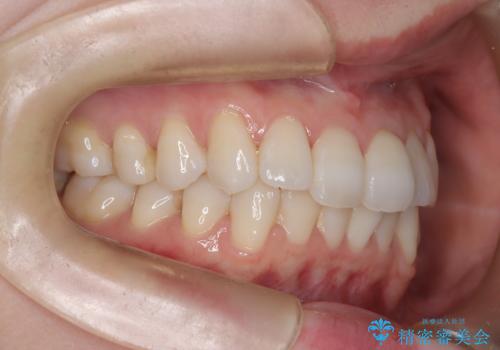

診査の結果、中等度の叢生であったため、インビザラインモデレートでの対応が可能と判断しました。

歯へのダメージを抑えるため、IPR(歯間削合)は必要最小限にとどめる方針としました。

前歯の叢生は解消され、自然で調和の取れた歯並びが得られました。